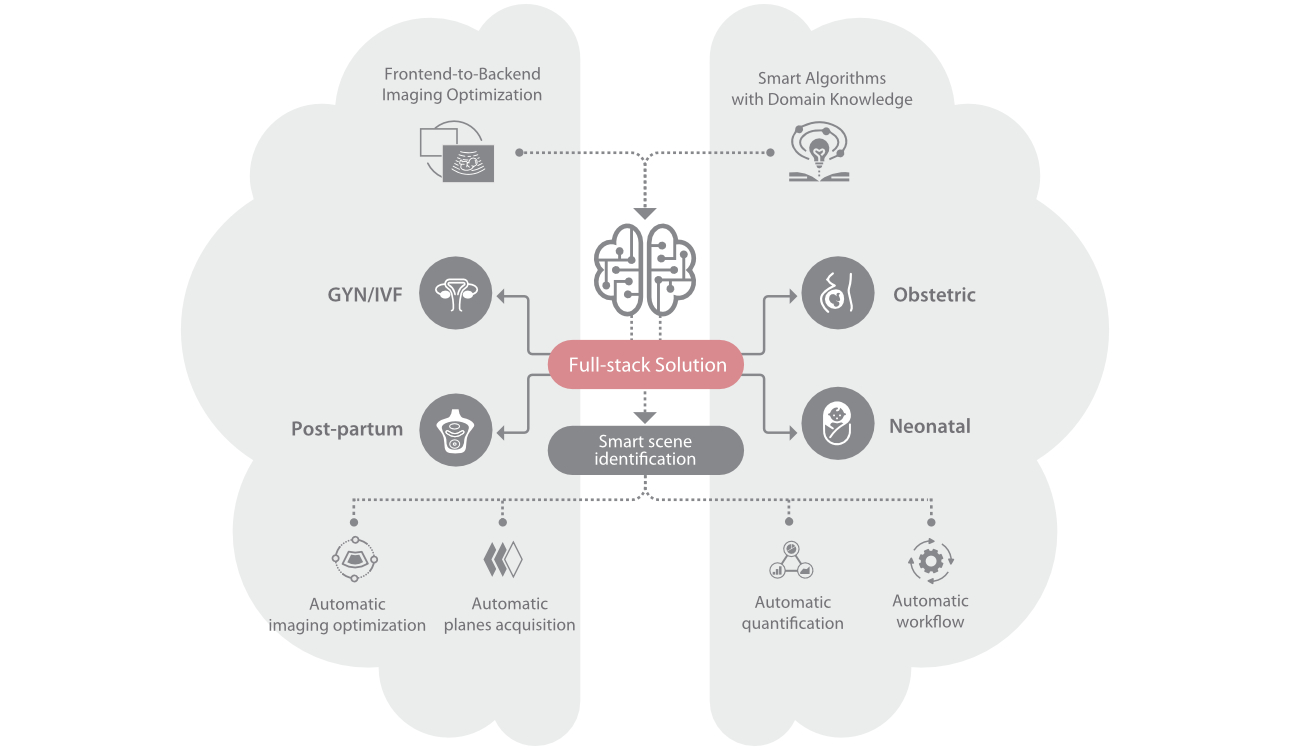

Nuewa I9, dirancang secara khusus untuk perawatan kesehatan wanita dan bayi baru lahir, menghadirkan pengalaman yang inovatif. Inovasi ini dikembangkan berdasarkan wawasan mendalam atas skenario klinis yang kompleks, memberikan jawaban yang akurat dan tepat waktu serta efisiensi dan pengalaman pengguna yang luar biasa.

Solusi lengkap yang Didukung oleh ZST +

Platform ZST+ merupakan inovasi luar biasa yang mewakili evolusi ultrasound. Mentransformasikan metrik ultrasound dari pembentukan cahaya konvensional menjadi pemrosesan berbasis channel data. Mengatasi batasan kompromi tradisional antara resolusi spasial, resolusi temporal, dan keseragaman jaringan, menghadirkan mutu gambar yang luar biasa untuk solusi pencitraan tak terbatas dengan peningkatan secara berkelanjutan.